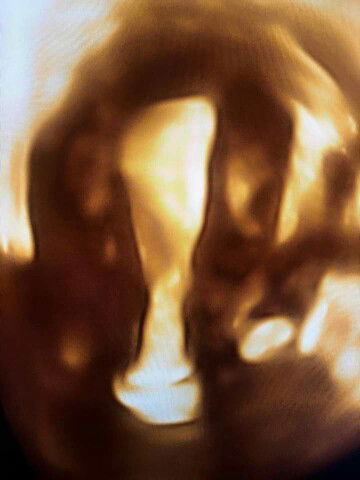

Ini ialah Ultrasound 4D rahim wanita yang baru saja selepas keguguran beberapa hari. Bila semua kehamilan sudah keluar, inilah dinamakan ‘complete miscarriage’ atau keguguran yang sudah lengkap. Tidak ada lagi kesakitan. Darah nifas sudah mula kering. Rahim sudah kecut ke saiz yang normal. Tidak ada peranakan jatuh dan kedudukan rahim Ini ialah normal. Dalam dinding rahim kelihatan licin saja. Tidak ada rahim yang kotor. Rahim tidak perlu diurut untuk kecut semula walaupun wanita ini tidak ada bayi untuk menyusu. Bila wanita ini tanya, perlukah berpantang 44 hari, saya jawab, tak payah pantang pun, sebab matlamat kita ialah kesihatan jangkamasa panjang. Dalam Islam hanya perlu pantang hubungan kelamin, solat, berpuasa sehingga darah nifas kering, kemudian mandi hadas besar. Rahim ini tak perlu di-urut, tak perlu disengkak, tak perlu dibetulkan kedudukannya. Untuk mengelakkan peranakan jatuh boleh lah buat senaman Kegels. Bila wanita ini kata beliau ada semangat baru untuk bersenam dan mengurangkan berat badan yang berlebihan, saya terus berikan galakan, boleh mulakan senaman dan tingkatkan intensiti senaman perlahan-lahan. Jangan lupa pemakanan sihat naaaaa. Jangan lupa positif selalu naaaaa. Jangan lupa ambil folik acid naaaaa. Boleh cuba untuk kehamilan lagi bila suami-isteri sudah bersedia. Ramai yang bertanya bila boleh mencuba kehamilan lagi selepas keguguran? Saya jawab, ini ialah berlainan untuk setiap pesakit, bergantung kepada tahap kesihatan mereka, jika ada obesiti, jika ada diabetes, jika ada penyakit autoimmune, jika ada jangkitan kuman, jika ada polycystic ovarian syndrome, jika merokok, jika perlukan ubat-ubatan untuk masalah perubatan. Jadi nasihat saya untuk setiap individu pesakit saya ialah berlainan. Jika anda seorang yang sihat, kajian perubatan telah membuktikan bahawa mereka yang hamil lagi sekali dalam masa 6 bulan selepas keguguran, tiada perbezaan risiko keguguran berulang jika dibandingkan dengan mereka yang memilih untuk menunggu sehingga 6 bulan untuk hamil lagi sekali. Memang tak payah berpantang cara lama selepas keguguran. Amalkan gaya hidup sihat dan cergas seumur hidup dan berfikir positif selalu. Saya doakan yang terbaik untuk anda, semoga mendapat kehamilan dan zuriat yang sihat selepas ini. Jangan lupa senyum selalu dan jangan salahkan diri sendiri. Dr Imelda Balchin, Pakar Kesihatan Wanita.